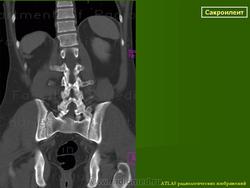

КТ КПС в корональной (а) и аксиальной (b) проекциях: правосторонний сакроилиит II стадии. http://congress-ph.ru/common/htdocs/upload/fm/rar/17/prez/A-10-02.pdf